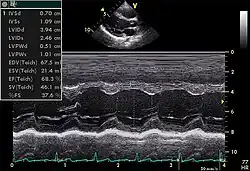

Le cœur est un organe tridimensionnel mobile. La prise en compte de cette quatrième dimension (le temps) est nécessaire pour une bonne appréhension de l'organe dans sa globalité. Cela nécessite une résolution temporelle suffisante pouvant être caractérisée par la cadence d'acquisition des images : elle doit être au moins d'une vingtaine images/s et idéalement supérieure à 50 images/s (pour permettre une visualisation correcte en ralenti, surtout si la fréquence cardiaque est élevée). De même, l'analyse à l'aide d'une image, par essence, bidimensionnelle, d'un organe quadridimensionnel, impose certains artifices : c'est le mode Tm (pour l' anglais : time motion), utilisé de manière courante, avec en abscisse le déroulement du temps et en ordonnée les échos détectés sur une seule ligne de tir.

- On en mesure les diamètres en systole et en diastole.

- On peut mesurer son volume, également en systole et en diastole : on somme le volume des disques successifs (de la pointe du cœur jusqu'à sa base) dont les diamètres sont estimés sur une coupe grand axe (Méthode de Simpson). En faisant le rapport (volume diastolique – volume systolique)/volume diastolique, on obtient la fraction d'éjection, indice important de la fonction contractile du muscle cardiaque.